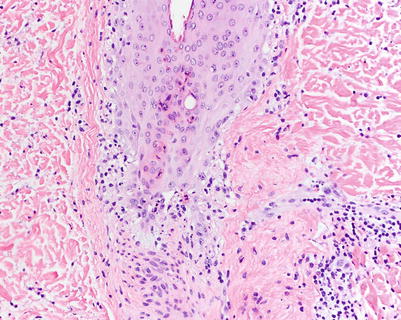

Fig. 5.3

Vacuolar interface change with necrotic keratinocytes within follicular epithelium in aGVHD (H&E, 200× magnification)